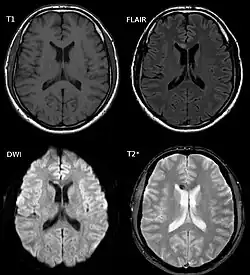

| Two MRI images of a patient with diffuse axonal injury resulting from trauma, at 1.5 tesla field strength. Left: conventional gradient recalled echo (GRE). Right: Susceptibility weighted image (SWI). | |

DAI is difficult to detect since it does not show up well on CT scans or with other macroscopic imaging techniques, though it shows up microscopically.[9] However, there are characteristics typical of DAI that may or may not show up on a CT scan. Diffuse injury has more microscopic injury than macroscopic injury and is difficult to detect with CT and MRI, but its presence can be inferred when small bleeds are visible in the corpus callosum or the cerebral cortex.[34] MRI is more useful than CT for detecting characteristics of diffuse axonal injury in the subacute and chronic time frames.[35] Newer studies such as Diffusion Tensor Imaging are able to demonstrate the degree of white matter fiber tract injury even when the standard MRI is negative. Since axonal damage in DAI is largely a result of secondary biochemical cascades, it has a delayed onset, so a person with DAI who initially appears well may deteriorate later. Thus injury is frequently more severe than is realized, and medical professionals should suspect DAI in any patients whose CT scans appear normal but who have symptoms like unconsciousness.[9]